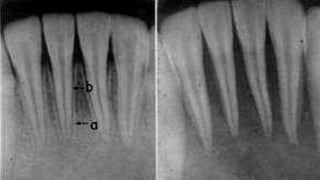

Anatomy of Apical Canal

According to Kuttler, the narrowest diameter of

the canal is definitely not at the site of exiting of the

canal from the tooth but usually occurs within the dentin,

just prior to the initial layers of cementum.

He referred to this position as the minor diameter

of the canal, although others call it the apical constriction.

The diameter of the canal at the site of exiting from the

tooth (major diameter) was found to be approximately

twice as wide as minor diameter. This means that the

longitudinal view of the canal as a tapering funnel to the

tip of the root is incorrect.